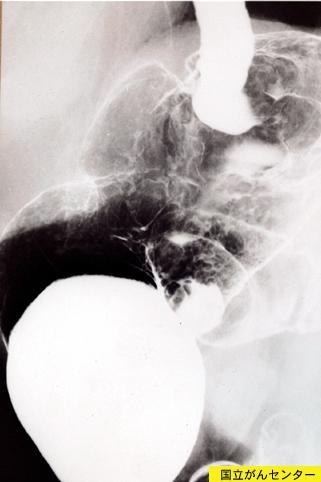

Criteria of Hist.ClassificationMalignant Lymphoma/Malignant lymphoma

LocationStomach/More than one of above

Technique, MethodX-ray

Size40 -

Depth of Tumor Invasionsubserosa (subadventitia)